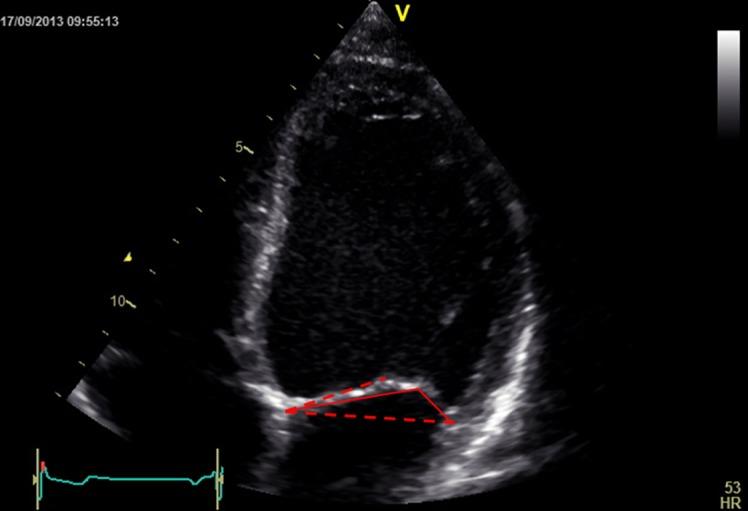

Quantitative analysis is an important part of the morphological assessment of the diseased mitral valve. It can be used to describe valve anatomy, pathology, function and the mechanisms of disease. Echocardiography is the main source of indirect quantitative data that is comparable with direct anatomic or surgical measurements. Furthermore, it can relate morphology with function. This review provides an account of current mitral valve quantification techniques and clinical applications.